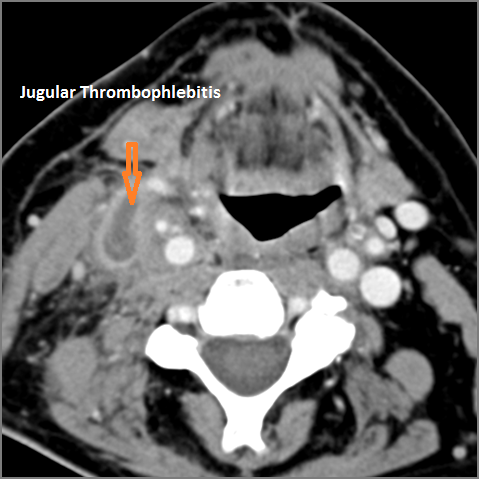

There is evidence of thrombus, thrombophlebitis or other occlusive or inflammatory process of the jugular vein or smaller venous tributaries. [Yes/No]